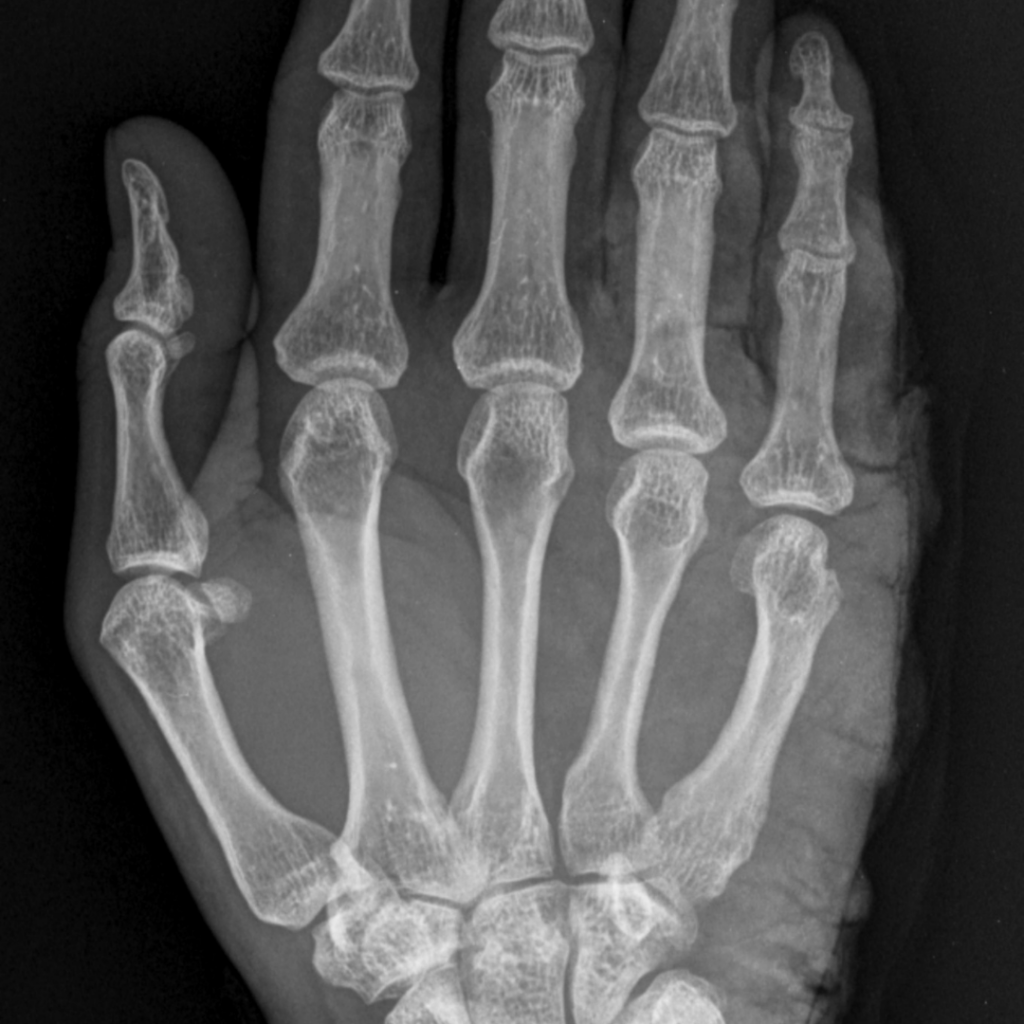

Perfect Diagnosis with New Imaging Technology

The entire management of fractures starts from their precise diagnosis. A thorough clinical examination is facilitated through digital X-ray imaging of fracture patterns, alignment, and joint involvement; where complex trauma cases may require advanced imaging to guide precise treatment.

Digital X-ray helps rule in early assessments and makes the choice between conservative and surgical management.